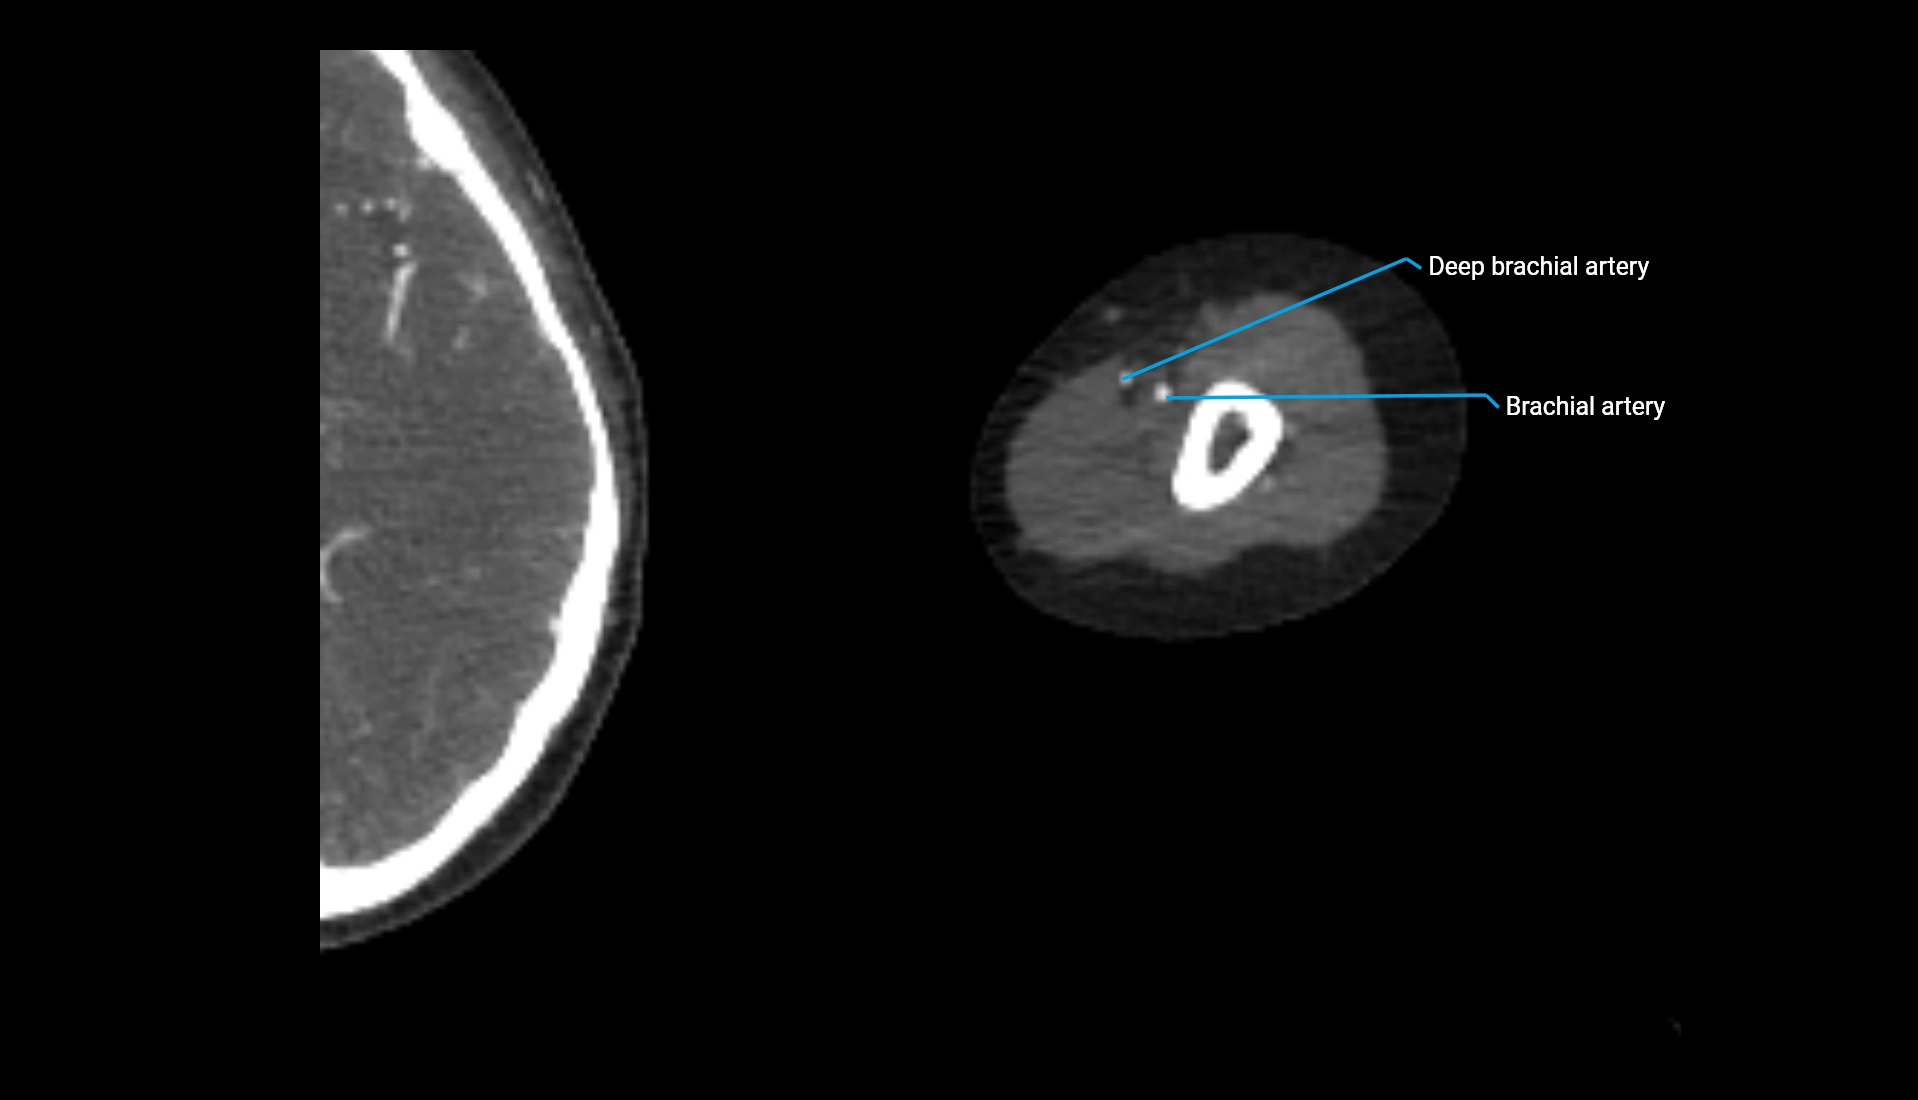

CT Appearance

Non-Contrast CT:

• Cortex: High-density, sharply defined

• Subchondral bone: Dense cancellous matrix

• Articular surface: Smooth concave contour articulating with the capitellum

• Excellent for evaluating bone integrity, alignment, and subtle fractures